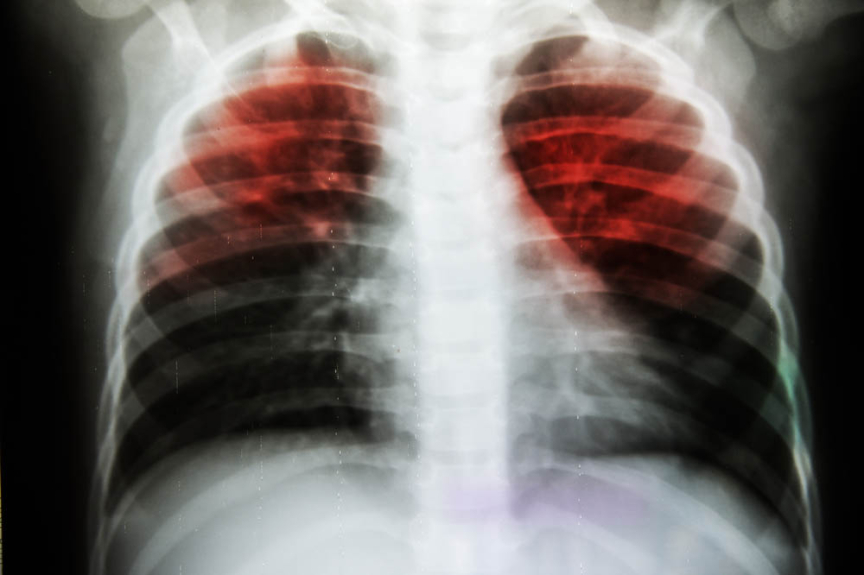

Tuberculosis, which mainly affects the lungs, kills more people worldwide — about 1.6 million — than any other single infectious illness.